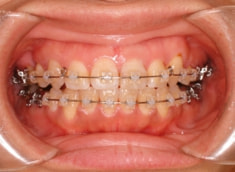

治療開始から約1年2ヶ月後